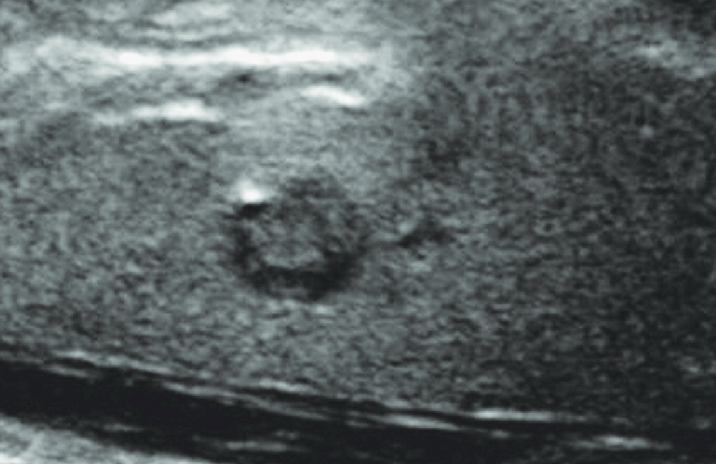

Thyroid Ultrasound

A thyroid ultrasound is typically the first imaging study performed when a nodule is detected. This noninvasive test evaluates the size, structure, and appearance of thyroid nodules and surrounding lymph nodes, helping determine whether further testing—such as biopsy—is needed.

Fine-Needle Aspiration (FNA) Biopsy

A fine-needle aspiration biopsy is the most reliable method for determining whether a thyroid nodule is benign or malignant. Using ultrasound guidance, a thin needle collects cells for microscopic analysis. At Providence Saint John’s Health Center, biopsy samples are evaluated promptly to support timely diagnosis and next-step planning.